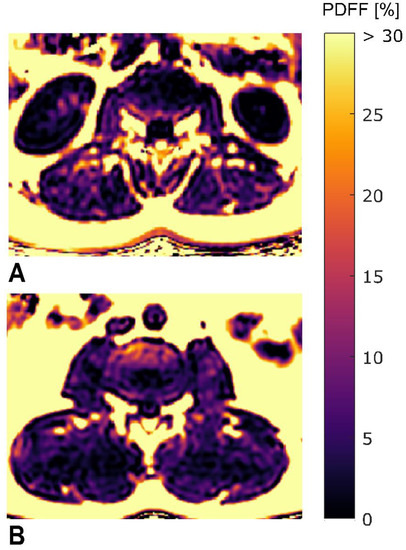

2.2. MR Imaging

2.3. MR Image Segmentation

2.4. Texture Analysis of PDFF Maps